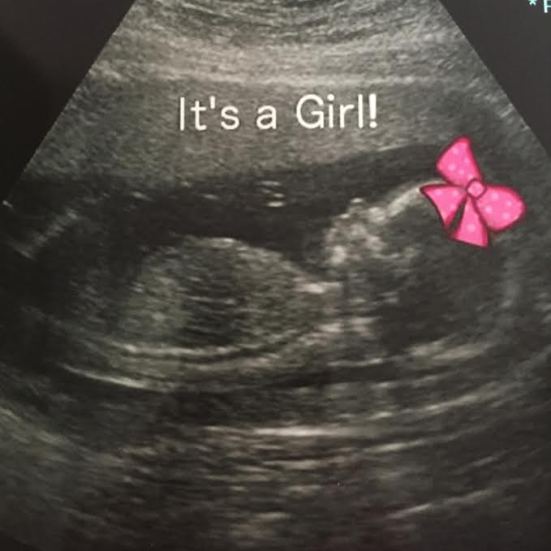

Kevin and I decided to change it up a little bit and do one of the fancy ultrasound places to determine the sex for Father’s Day. Everyone was thinking it’d be mid-July before we knew, so we wanted to really surprise all of the awesome men in our lives with the news.

Holy shit – we’re having a baby girl.